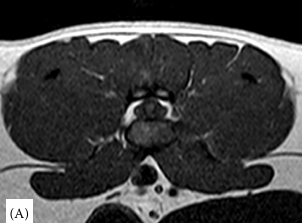

연구 대상은 4세 장모 고양이로 갑작스러운 좌측 후지 절뚝거림과 점프 회피 증상을 보였다. MRI 검사 결과, L6–L7 추간판이 원외측으로 탈출해 신경근을 압박하고, 국소 염증을 동반한 사실이 밝혀졌다. 이는 지금까지 개에서만 드물게 보고된 질환으로 고양이에서는 최초 사례다.